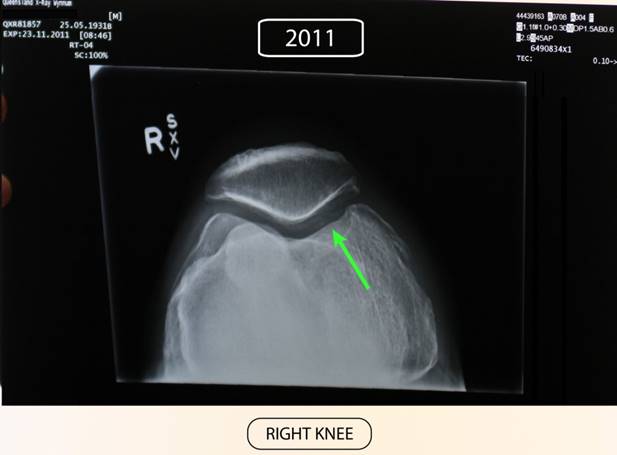

OSTEOARTHRITIS and OSTEOPOROSIS.

Before Stem Enhance ULTRA.

After Stem Enhance ULTRA.

81 Year old with Pre-existing Osteoarthritis and Osteoporosis

Before commencing supplementation he was seeing a specialist preparing for knee replacement.

Taken Stem Cell Nutrition for 7 months. 2 capsules of StemEnhance ULTRA in the morning and again 2 StemEnhance ULTRA at night.

Had another xray taken 7 months later and following this period of supplementation he was advised by the specialist that he no longer required a knee replacement as all the cartlidge had grown back and the bone density repaired. (See the green arrow area on both pictures.)